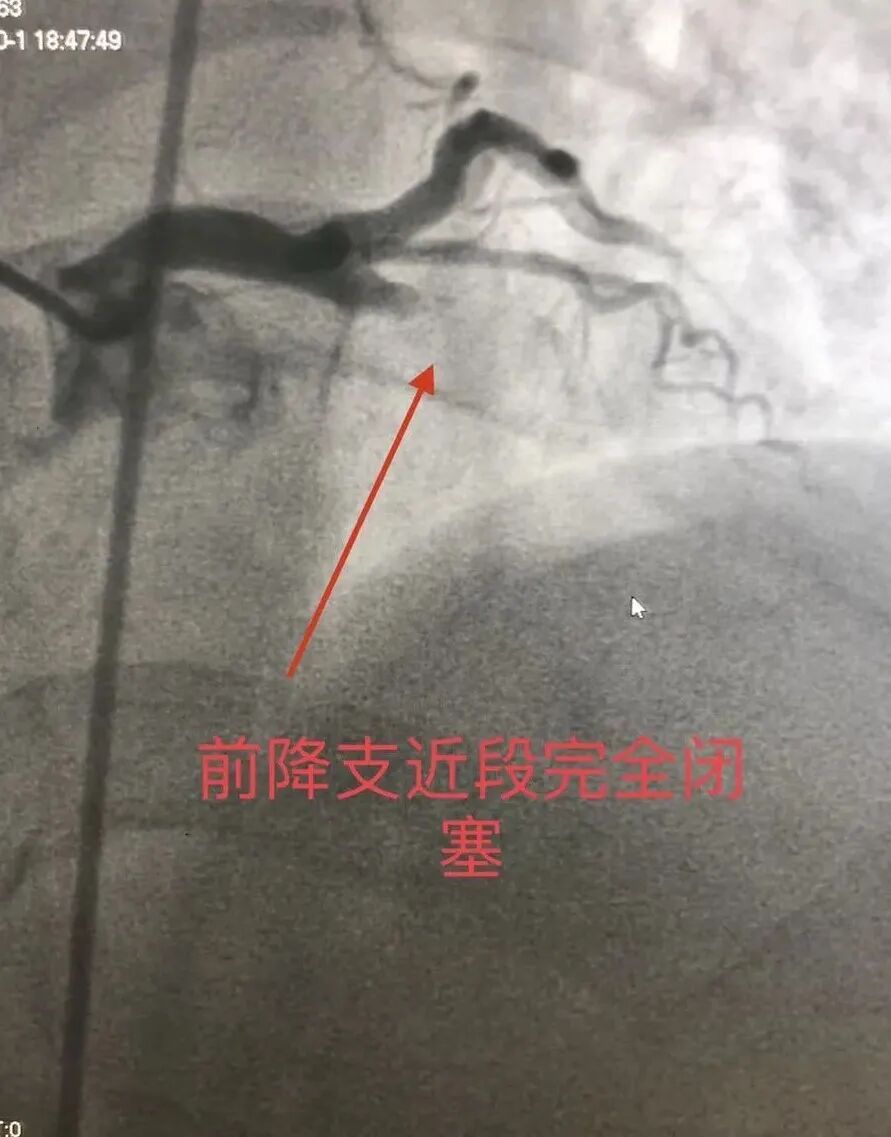

“陈先生前降支近段完全闭塞,随时可能再次发生室颤,甚至猝死。”术中,修建成教授团队沉着冷静,一边嘱加强监护、呼吸机辅助呼吸,给予升压药物维持血压,一边迅速扩开闭塞血管,植入支架……

▲术中左冠状动脉造影见前降支近段完全闭塞